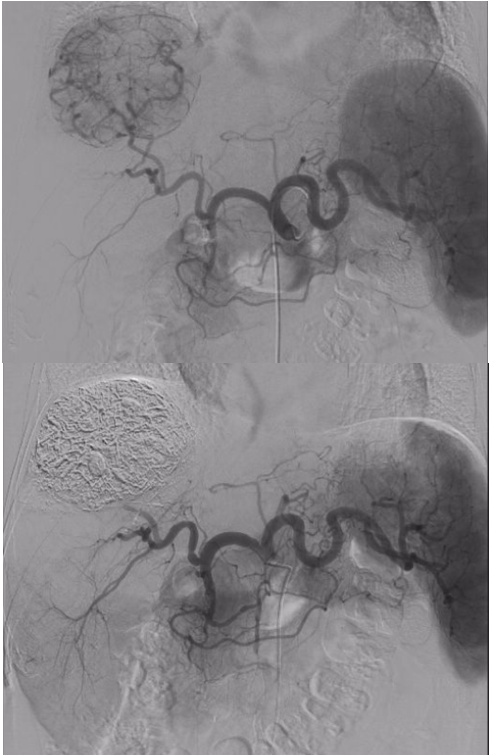

Hình ảnh chụp mạch máu trước và sau khi TACE